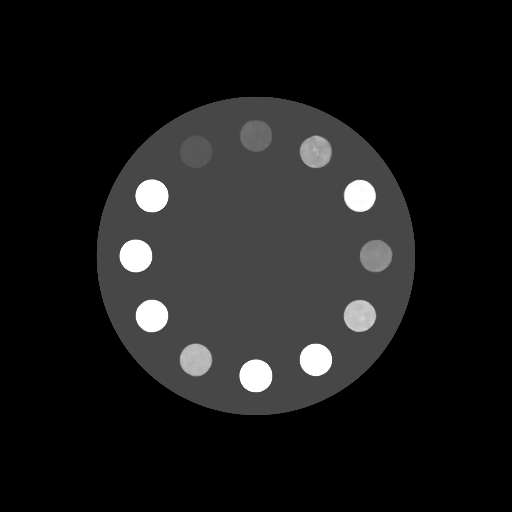

(20-cm cylindrical phantom)

(30-cm cylindrical phantom)